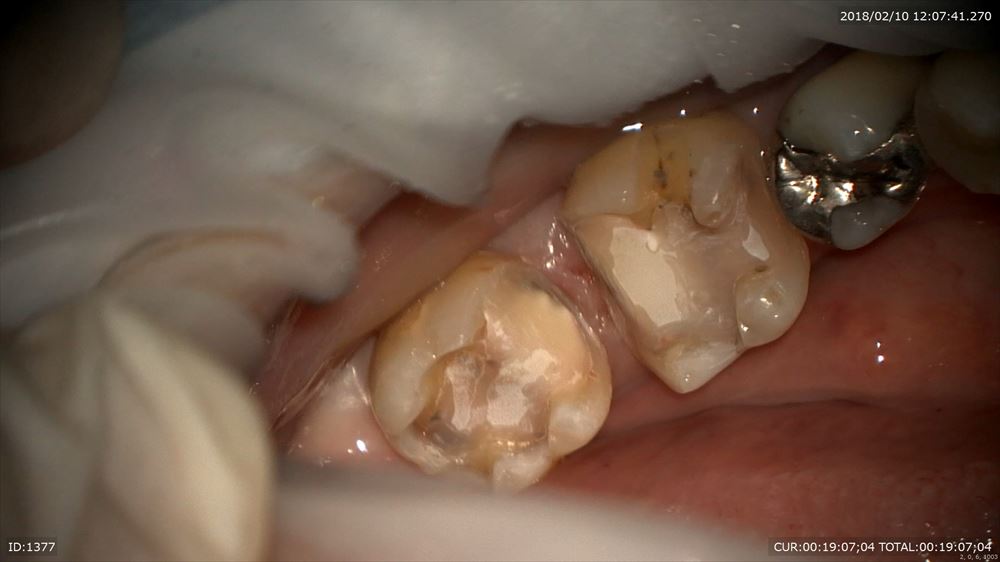

銀歯虫歯の方。

銀歯の中は

こうなっています。

これもマイクロスコープを使用し無痛で感染除去 MTAで

これで型とり。大丈夫!!